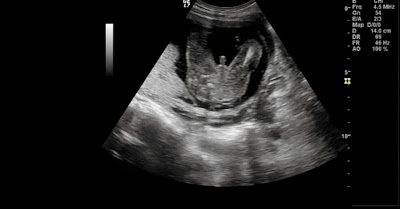

Eco morfológica 21 semanas

Ontem foi dia da ecografia mais aguardada, a expectativa era tão grande...acho que nestes dias nem dá para dormir decentemente (ou isso, ou eu já sou uma mãe galinha do pior!)

depois de contar cada minuto do dia, a hora da eco chegou e o meu coração quase saltava do peito!

a primeira imagem foi logo esta, acompanhada das palavras do médico "eh lá, não há dúvidas que é um pilas!"

Estava tudo óptimo com ele, vimos todos os pedacinhos e todos os orgãos e nunca é demais...sabe tão bem!

Portanto, o Guilherme está ali para ficar, é gorducho (480gr) e super mexido, foi uma festa.

Mais uma grande etapa ultrapassada :D!